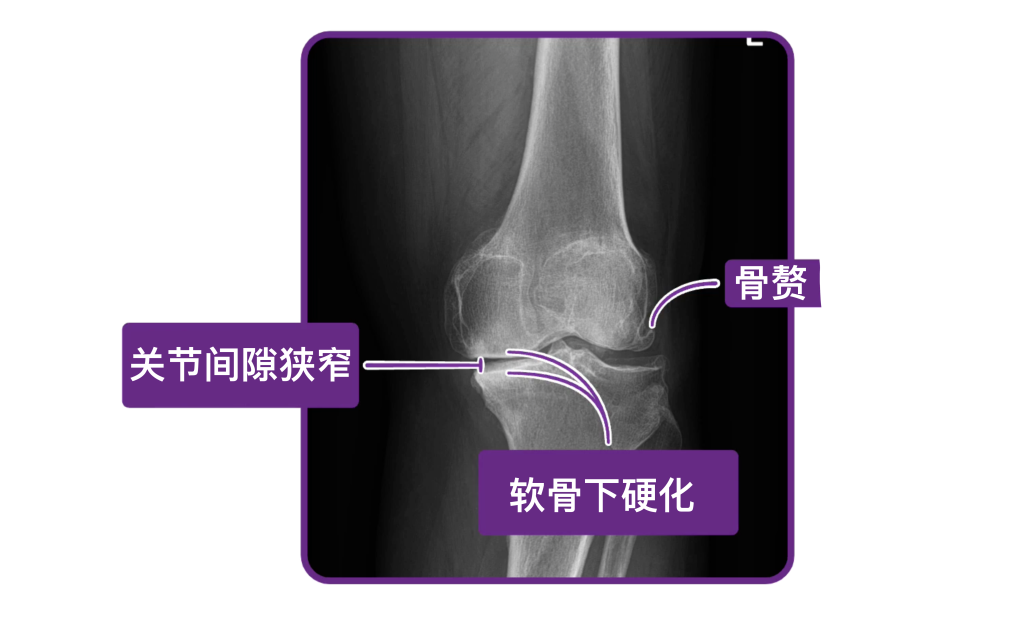

如果病史和体格检查结果与骨关节炎一致,则无需进一步检查,即可做出骨关节炎的诊断。但如果诊断不明确,就应为受累关节拍摄X线片。如果X线结果与骨关节炎不符,就要考虑其他诊断。相反,如果X线显示关节间隙变窄、骨赘形成以及软骨下硬化,就可以诊断为骨关节炎。

这里有一个临床要点:在骨关节炎患者中,X线所见与临床症状并不总是相符。例如,X线可能提示关节严重损伤,但患者可能只表现出轻微的症状。